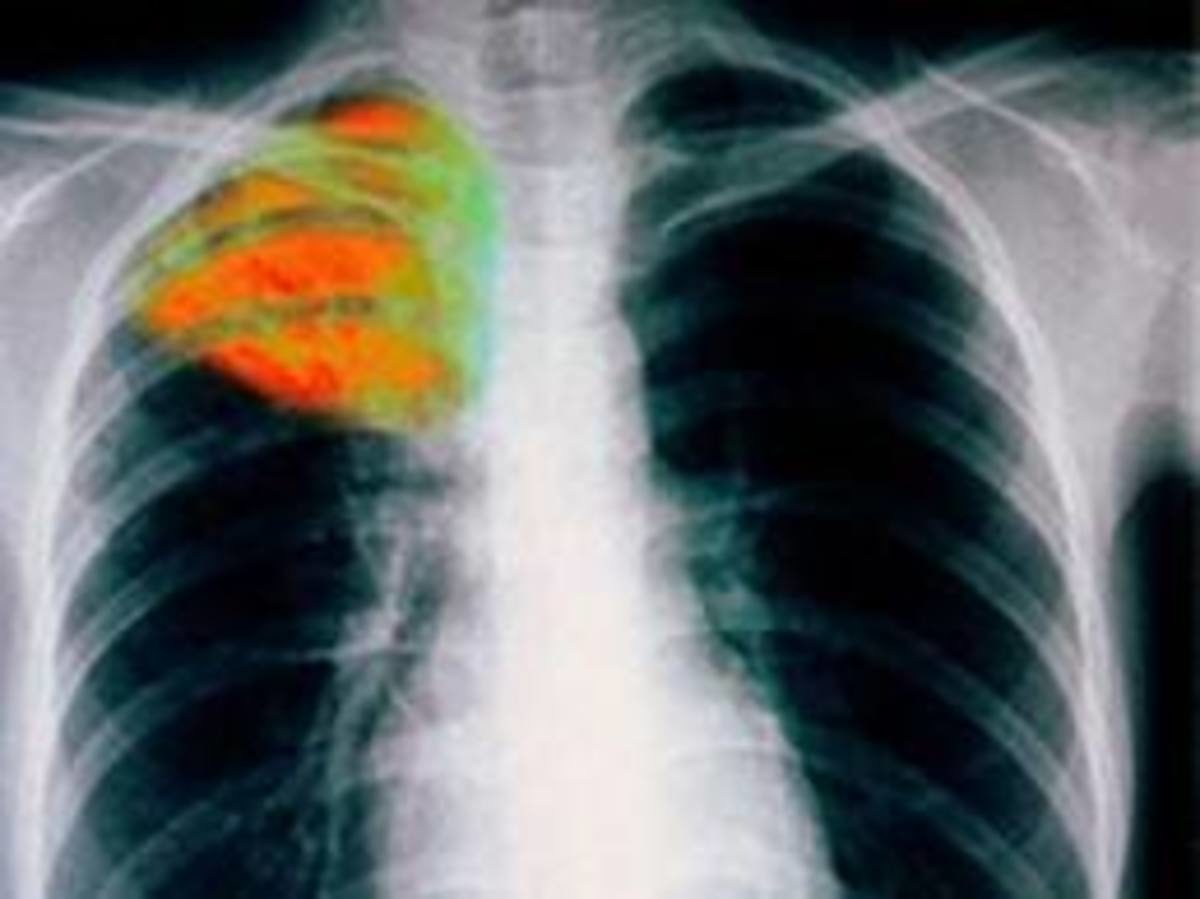

Ένα νέο τεστ για την διάγνωση φυματίωσης που ανέπτυξαν Καναδοί ερευνητές δίνει αποτελέσματα σε ώρες αντί για ημέρες ή εβδομάδες.

Ο απαιτούμενος εξοπλισμός για την διενέργεια του τεστ δεν ξεπερνά το μέγεθος ενός σκληρού δίσκου υπολογιστή όμως το τεστ της GeneXpert ανιχνεύει το DNAτων βακτηρίων που προκαλούν την νόσο στο δείγμα πτυέλων με επιτυχία που φθάνει το 85% και μάλιστα σε ώρες αντί για μέρες ή εβδομάδες που απαιτούσε η συνήθης μικροβιολογική καλλιέργεια.